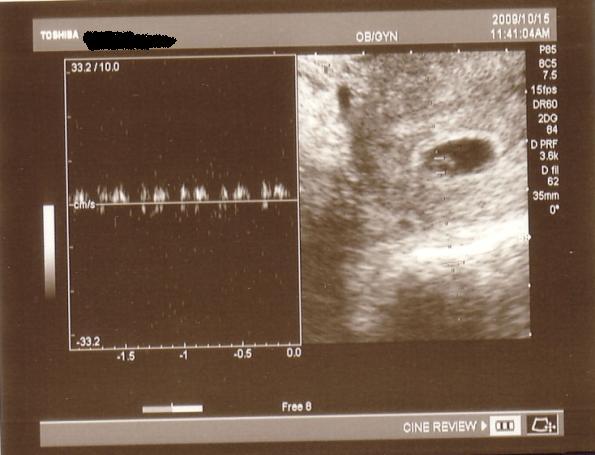

A babával minden rendben van,már fél centi,a petezsák szabályos,találtak szívcsőpulzációt,csak éppen felette van egy hematóma, ami elkezdett vérezni.A doki szerint gyakori,kaptam rá gyógyszert a többi mellé.Most szigorúan feküdnöm kell,két hét múlva hívott vissza kontrollra,akkor kiderül felszívódott-e.

A babával minden rendben van,már fél centi,a petezsák szabályos,találtak szívcsőpulzációt,csak éppen felette van egy hematóma, ami elkezdett vérezni.A doki szerint gyakori,kaptam rá gyógyszert a többi mellé.Most szigorúan feküdnöm kell,két hét múlva hívott vissza kontrollra,akkor kiderül felszívódott-e.

Princzi, már volt pulzálás??? Jaj, de jóóó, és ilyen korán???

Princzi, már volt pulzálás??? Jaj, de jóóó, és ilyen korán???